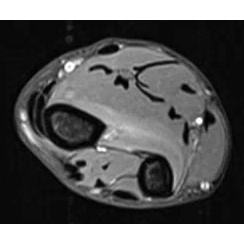

| On Your Last Nerve With Forearm Weakness - Page #3 | |||